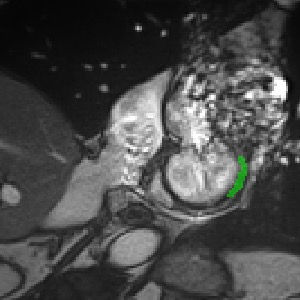

Transformers, the default model of choices in natural language processing, have drawn scant attention from the medical imaging community. Given the ability to exploit long-term dependencies, transformers are promising to help atypical convolutional neural networks (convnets) to overcome its inherent shortcomings of spatial inductive bias. However, most of recently proposed transformer-based segmentation approaches simply treated transformers as assisted modules to help encode global context into convolutional representations without investigating how to optimally combine self-attention (i.e., the core of transformers) with convolution. To address this issue, in this paper, we introduce nnFormer (i.e., Not-aNother transFormer), a powerful segmentation model with an interleaved architecture based on empirical combination of self-attention and convolution. In practice, nnFormer learns volumetric representations from 3D local volumes. Compared to the naive voxel-level self-attention implementation, such volume-based operations help to reduce the computational complexity by approximate 98% and 99.5% on Synapse and ACDC datasets, respectively. In comparison to prior-art network configurations, nnFormer achieves tremendous improvements over previous transformer-based methods on two commonly used datasets Synapse and ACDC. For instance, nnFormer outperforms Swin-UNet by over 7 percents on Synapse. Even when compared to nnUNet, currently the best performing fully-convolutional medical segmentation network, nnFormer still provides slightly better performance on Synapse and ACDC.